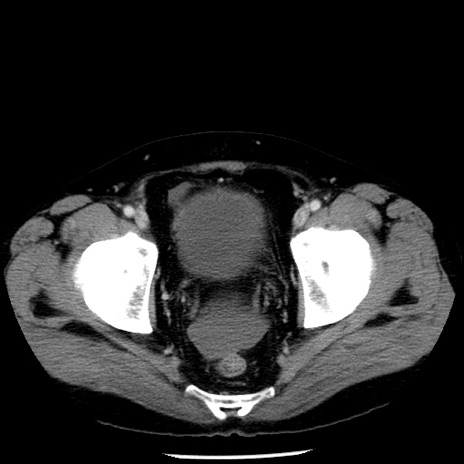

症例29(横断像)

【症例】40歳代男性

【現病歴】2日前から胃痛あり。徐々に周期的な激痛に変化した。本日になっても激痛があるため受診。

【身体所見】意識清明、BT 38-39℃台あり、腹部:膨満、やや硬、右下腹部に圧痛あり。

【データ】WBC 8500、CRP 23.26